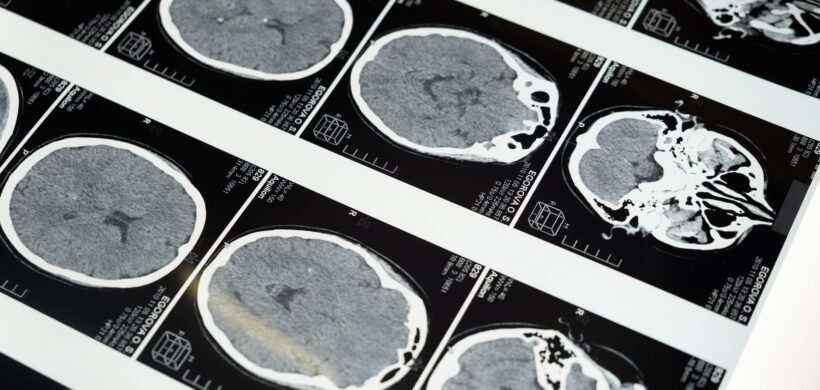

Urrutia Amable a, S. Sosa Pérez a, D. López Brito a, A I. Peñalver Guía b, G. Bringas Sánchez b, L. Pérez Ruiz c, T. Rodríguez Obaya c, Carmen M. Valenzuela Silva c y A. Fernández Nin d | a Hospital General Docente Iván Portuondo, San Antonio de los Baños, Artemisa, Cuba. b Instituto de Neurología y Neurocirugía (INN), La Habana, Cuba. c Centro de Inmunología Molecular (CIM), Playa, La Habana, Cuba. d Centro de Neurociencias de Cuba (CNEURO), La Habana, Cuba. La enfermedad de Alzheimer (EA) es considerada actualmente la forma más común de demencia en los adultos mayores, representando alrededor del 60 al 70% de los casos. El enfoque terapéutico o farmacológico de la EA actualmente es sintomático y no curativo. Disímiles ensayos clínicos con diversos productos para el tratamiento de la EA han fracaso, otros aún continúan en la búsqueda de eficacia, seguridad o una posible cura. Desde finales del siglo pasado en nuestro país se produce la eritropoyetina humana recombinante (EPOhr), con diversos resultados científicos que han demostrado su acción hematopoyética, neuroprotectora, antioxidante, anti-inflamatoria, neurotrófica y angiogenética. Debido a ello se decidió desarrollar una eritropoyetina con bajo contenido de ácido siálico no hematopoyética (NeuroEPO); ampliamente estudiada con iguales acciones neuroprotectoras que su antecesora. El presente estudio tiene como objetivos principales evaluar la eficacia del tratamiento con NeuroEPO en pacientes cubanos con síndrome demencial tipo Alzheimer leve/moderado, en términos de la reducción en la progresión del deterioro cognitivo; así como determinar su efecto en las manifestaciones psicoconductuales. Participaron 174 pacientes con diagnóstico de síndrome demencial tipo Alzheimer leve/moderado como parte de un ensayo clínico, aleatorizados en 3 grupos con 58 pacientes cada uno: A y B recibieron dosis de 0,5 mg y 1 mg respectivamente; y C recibió placebo. Se demostró la eficacia del tratamiento con NeuroEPO, con diferencias en el puntaje del ADAScog11 al finalizar el estudio de 8 y 9 puntos en los grupos tratados con relación al grupo placebo (p=0.000, IC 95%) en la población por protocolo, mejorando también el porcentaje de cambio del CIBIC Plus (p=0.000, IC 95%), con resultados significativos en el resto de las pruebas neuropsicológicas realizadas. Además, éstos lograron una disminución de la sintomatología psicoconductual (p=0.000, IC 95%) respecto al grupo control. Como conclusiones fundamentales se evidenció una reducción en la progresión del deterioro cognitivo en los grupos que recibieron NeuroEPO con relación al grupo placebo, reflejada en la mejoría cognitiva y psicoconductual al finalizar el estudio. Acceso al artículo completo.